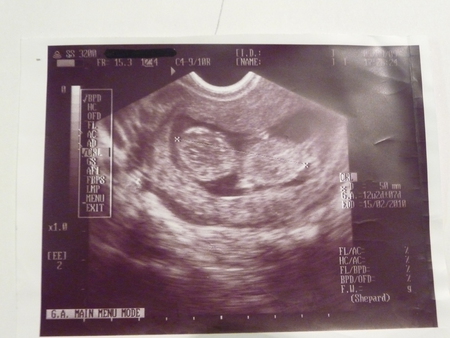

Следущее фото было сделано когда моему сыночку было 12 недель, он был вот таким

Тут он 50 мм,мой маленький карапуз.